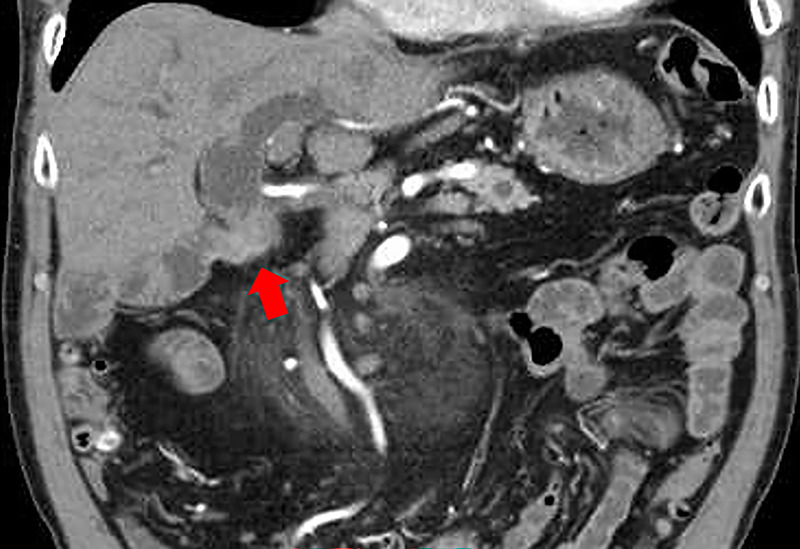

Successful EUS-guided fine-needle biopsy using a forward-viewing echoendoscope for local recurrence at the choledochojejunal anastomotic site 13 years after pancreaticoduodenectomy for cholangiocarcinoma.

胰十二指肠切除术治疗胆管癌13年后胆肠吻合口局部复发,超声引导下前视超声内镜下细针活检成功。